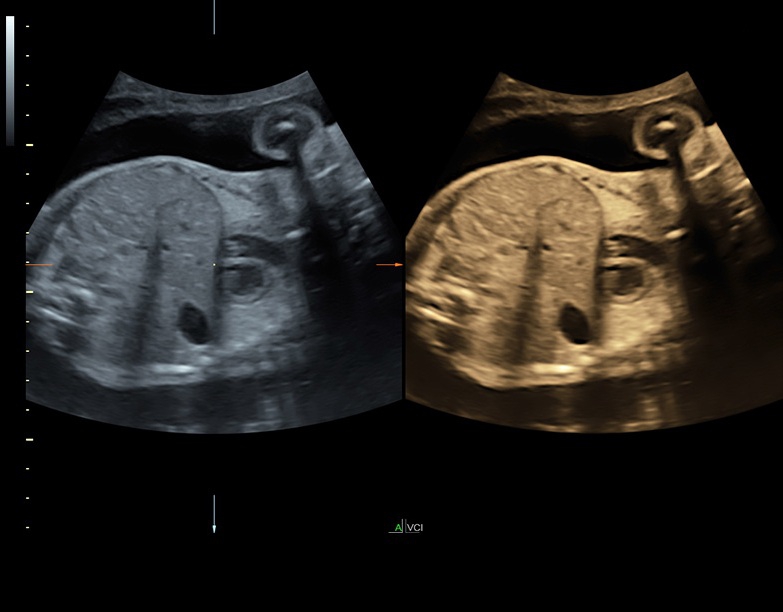

Ультразвуковая платформа Voluson S8 представляет собой оборудование экспертного класса с передовыми возможностями и высоким уровнем автоматизации процессов. Она позволяет проводить сканирование в режимах 2D, 3D и 4D с высоким качеством изображений.

Аппарат Voluson S8 базируется на надежной платформе VCA, которая имеет множество положительных отзывов. Она обладает высококонтрастной технологией объемной реконструкции, обеспечивая качественное воспроизведение изображений. Информация выводится на широкоформатный цветной монитор размером 23 дюйма для убедительной демонстрации плода будущим родителям и облегчения работы врача.

• Технология SonoRenderlive: Эта технология облегчает получение 3D/4D изображений путем автоматического изменения положения плоскости визуализации в зависимости от движений плода. Она позволяет получить реалистичные и объемные изображения, что полезно для демонстрации плода будущим родителям и для дополнительного анализа.

• HDlive в 3D и 4D - режим перемещаемого виртуального источника освещения - "виртуальная фетоскопия"

• Расширенный программный пакет объемного контрастного изображения (VCI) для объемных датчиков